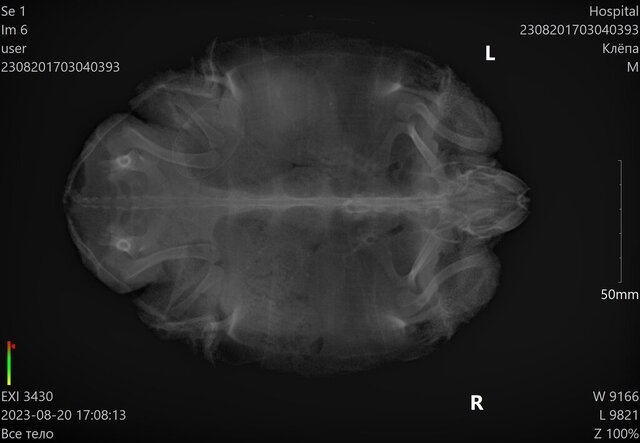

Даша17 Ваше имя: Дарья Локация: Россия, Зеленоград Опубликовано: 8 февраля 2023 Автор Опубликовано: 8 февраля 2023 @moth Зеленоград (Москва), 28 2. Красноухая 3. Акватеррариум 150 литров воды (именно воды) 41. Лампа накаливания есть над островом, работает где-то 12 часов 4.2. УФ лампа sylvania reptistar 10 (лампе 7 месяцев) 4.3. Берег встроенный 4.4. да, aquael ultramax 1000 4.5. Да, JBL, 25 градусов в воде грунт крупные камни 5. Температура 25 вода, на суше не знаю, но там лампа накаливания, тепло 6. С детства питание было рептомин, сначала бэби, потом джуниор, стикс, sera carnivor . Изредка (пару раз в месяц) были тигровые креветки, морковь, сверчки, гуппи живые. 7. Черепахе (девочке) 4 года, весит 980 г 8. С лета черепаха очень плохо ест. Последние полгода пытались кормить чем придётся- судак и щука сырые, тигровые креветки сырые, потом она и от них отказалась, на рептомин не реагирует вообще даже через голодовку 2 недели, серу может съесть 1 штуку в 2 дня, дальше уже выплёвывает. Подселили ей рыбок живых, она съела одну, вторую просто убила и не съела, с остальными уже 2 недели живёт в ладу. Никакое мясо никогда не давали. Летом ездили к врачу, врач заподозрила проблемы с яичниками и заметила компрессию лёгких, но подумали, что это из-за яичников. На прошлой неделе ездили в клинику, сделали повторный рентген (есть только эти свежие снимки, летних нет), и анализ крови (биохимия и общий). На рентгене замутнение в лёгких, я так поняла, как и летом. Испражняется черепаха на сходню острова, незаметно для нас, но стабильно сходня пачкается. Плавает без уклонов, дышит нормально, шею не раздувает, не кашляет. Один раз за эти полгода она чихнула и вылетело что-то на стекло, это было месяца 3 назад. По осмотрю внешнего вида врач дефектов не обнаружила. Сделали укол Элеовит 0.5 мл в попу. Прилагаю снимок и анализ крови, хотела бы узнать мнение, что может быть с черепахой